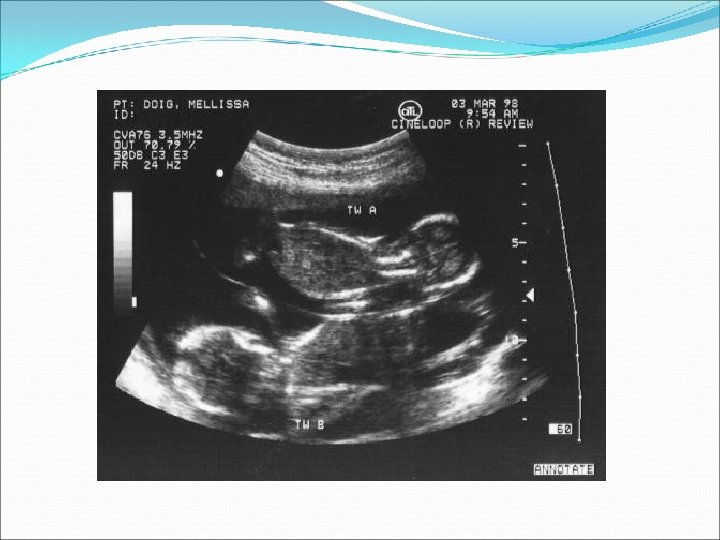

Ø Auscultation of two fetal heart beats at two different sites with a difference of 10 beats Ø USS Two sacs by 5 weeks by TV USS. Two embryos by 7 weeks by TV USS.